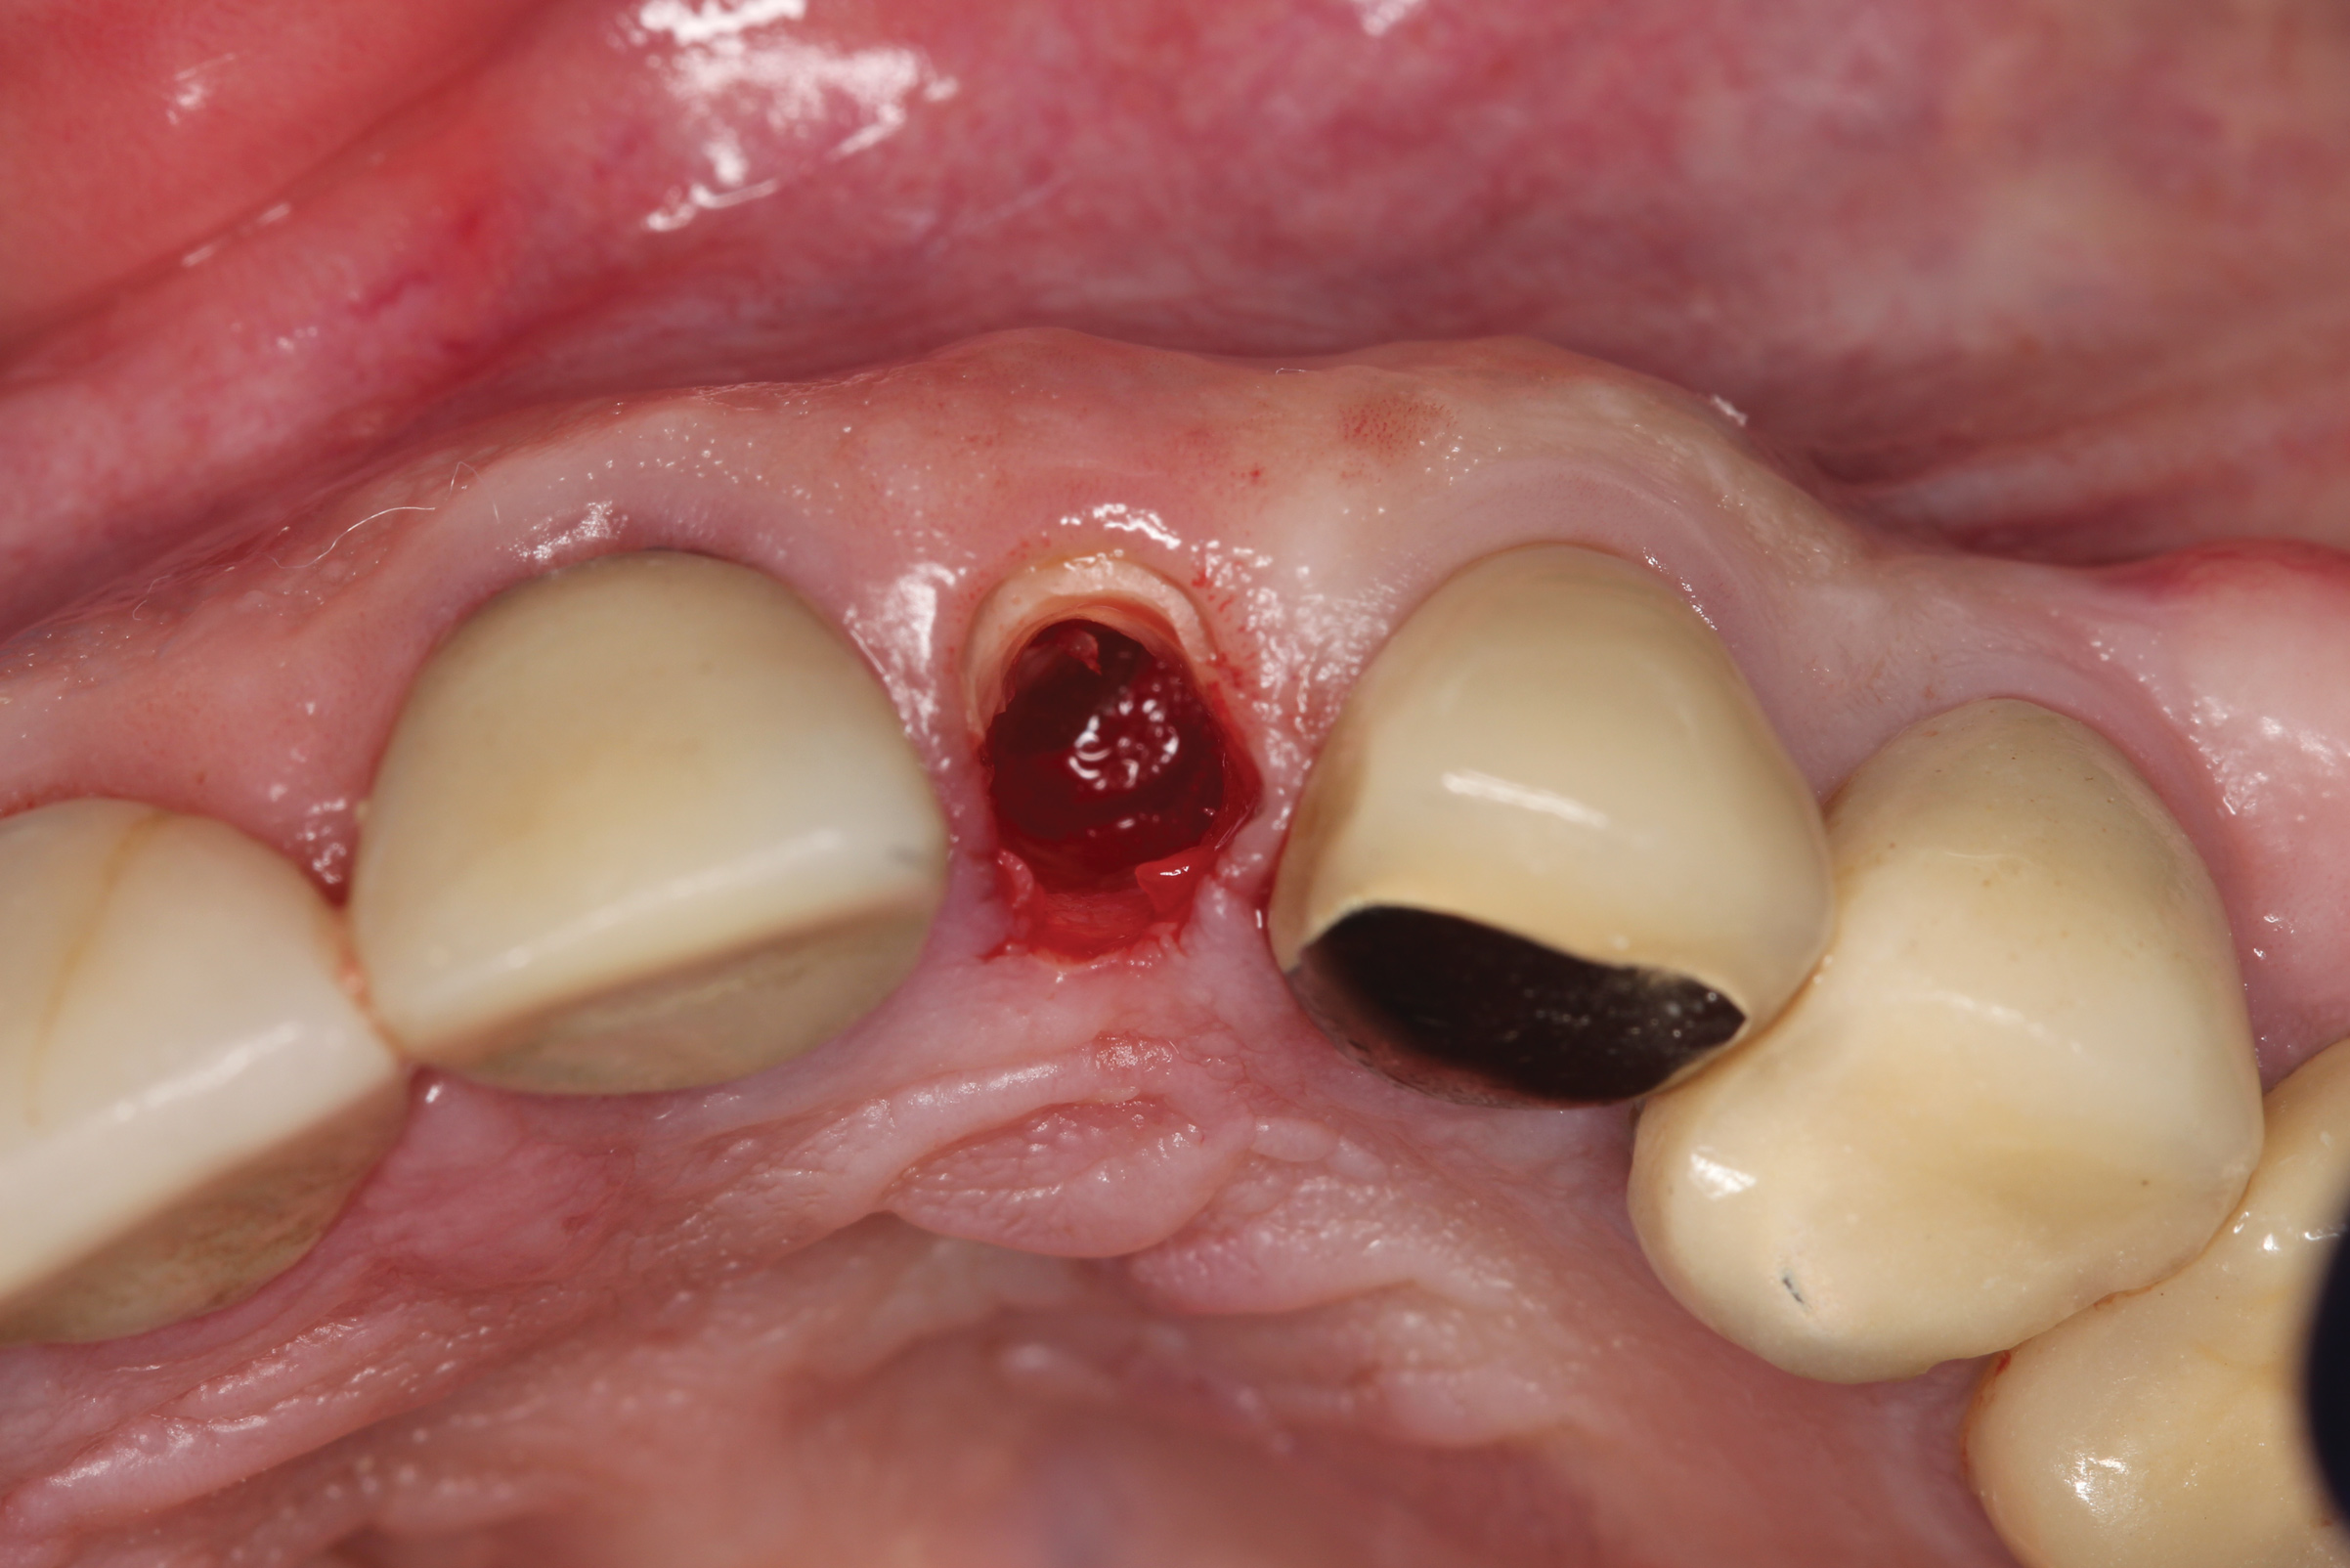

Fig 16. Patient presented with fractured maxillary left lateral incisor. Radiographic analysis (not shown) revealed minimal buccal bone. A socket shield was planned during tooth extraction to preserve gingival contours.

Figure 16

Fig 17. The root was sectioned mesial-distal, followed by removal of the palatal root half.

Figure 17